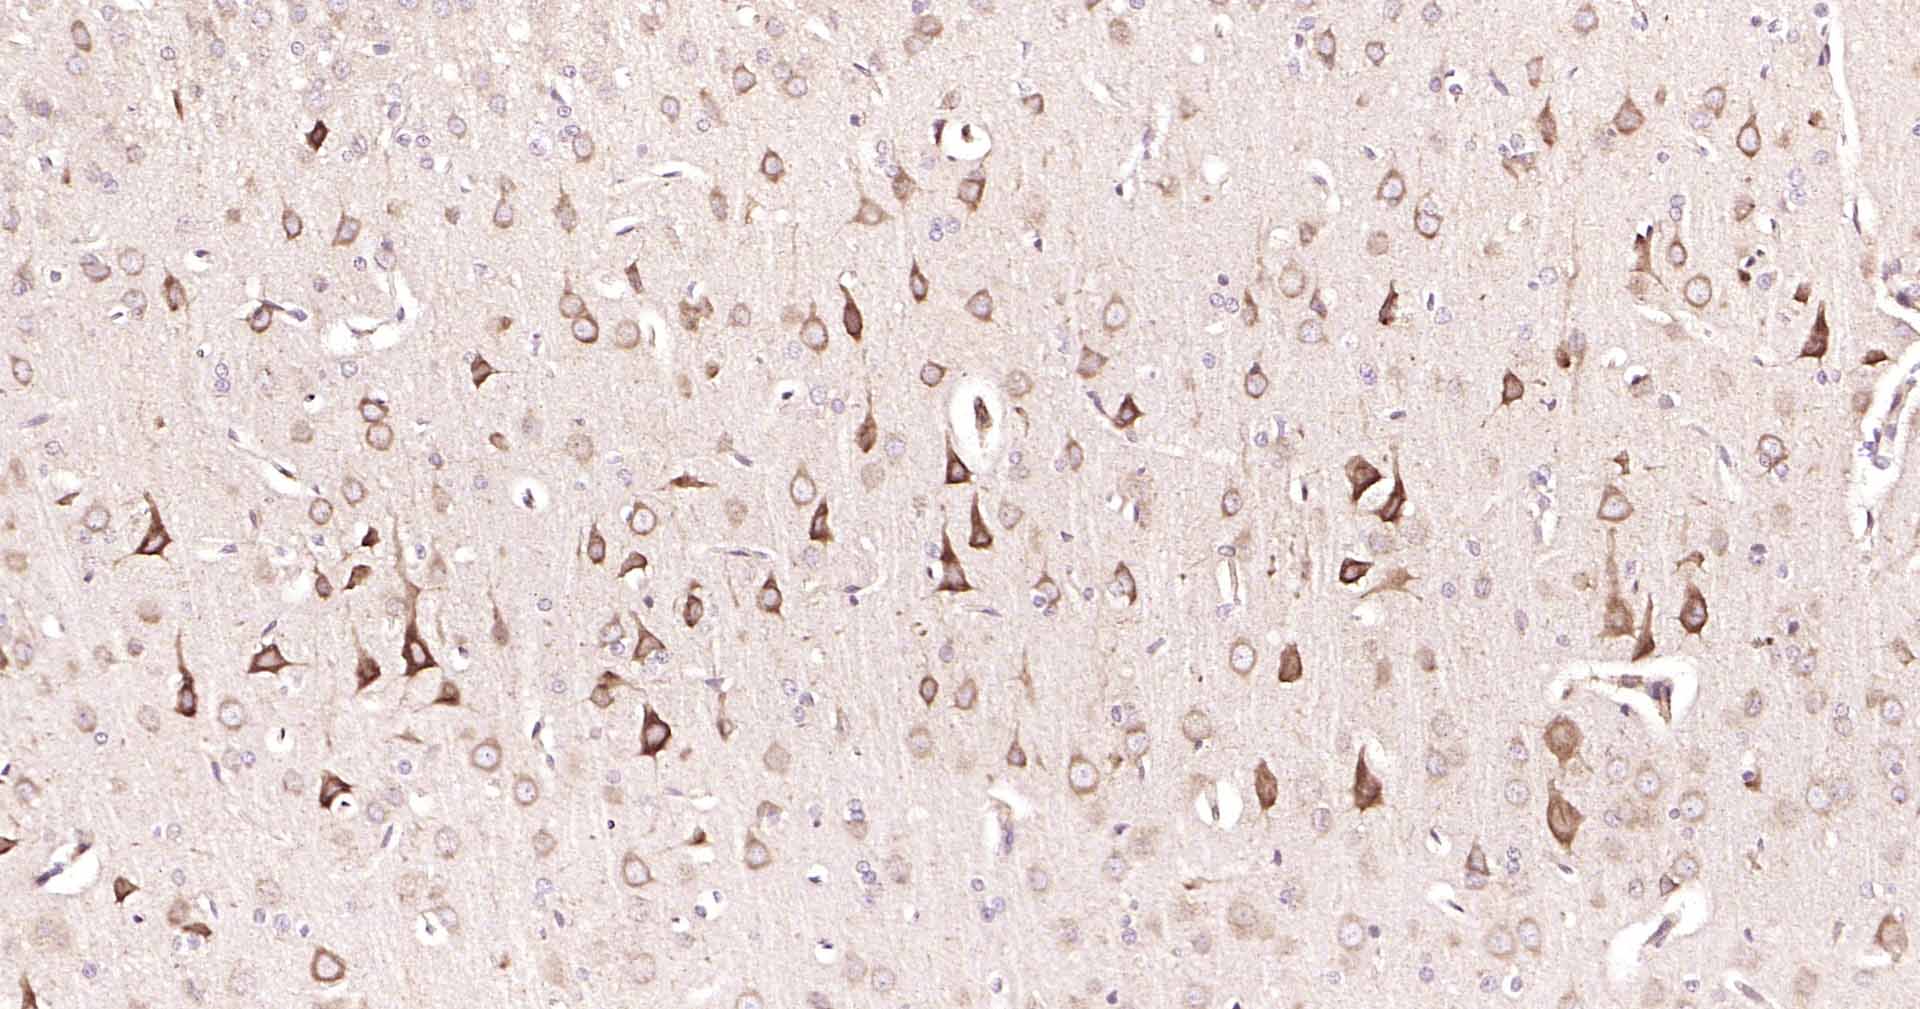

GADD153抗体-bs-20669RGADD153抗体-bs-20669RGADD153抗体-bs-20669RGADD153抗体-bs-20669RGADD153抗体-bs-20669RGADD153抗体-bs-20669RGADD153抗体-bs-20669RGADD153抗体-bs-20669RGADD153抗体-bs-20669RGADD153抗体-bs-20669RGADD153抗体-bs-20669R

IHC-PHuman, Mouse, RatCow1:50-200

IHC-FHuman, Mouse, RatCow1:50-200

亚细胞定位

Cytoplasm. Nucleus. Note=Present in the cytoplasm under non-stressed conditions and ER stress leads to its nuclear accumulation.